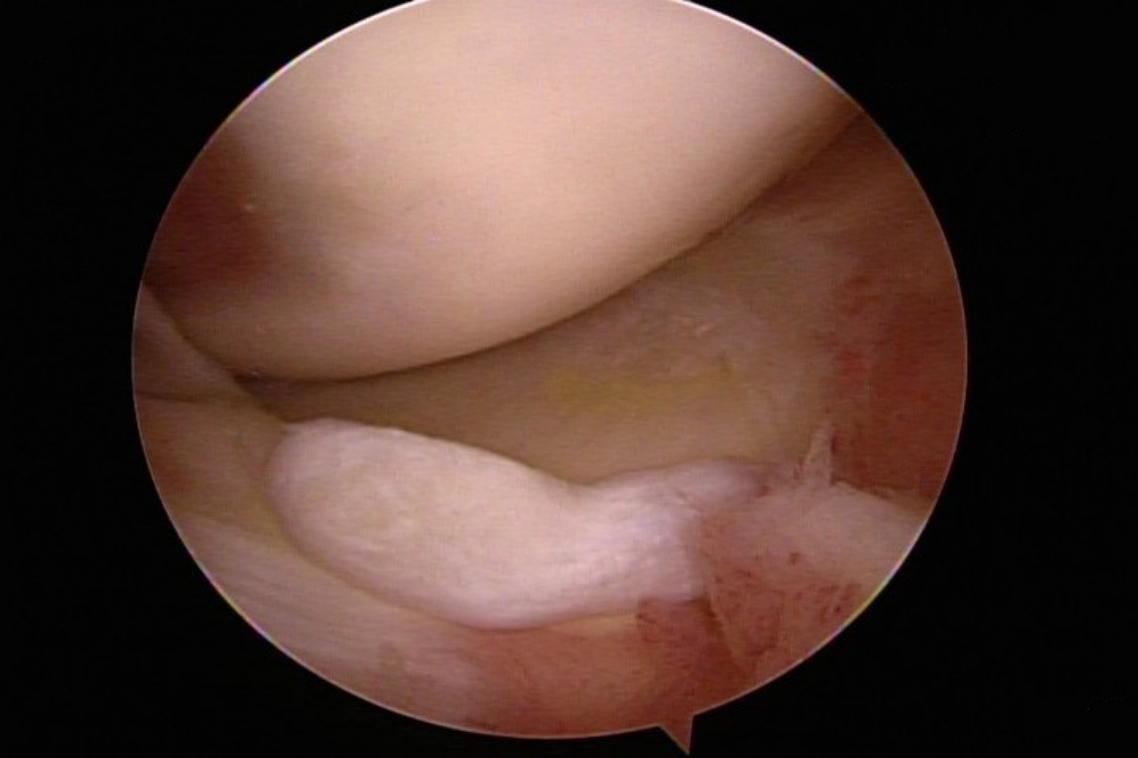

軟骨碎片與發炎滑膜(圖片來源/林心畬醫師提供)

台北市立聯合醫院忠孝院區骨科主治醫師林心畬表示,輕微的磨損注射玻尿酸潤滑即可緩解,但較嚴重的損傷會導致軟骨破裂,有時軟骨會移位,碎片會脫落,形成大問題。關節軟骨出現較大破損時,會有明顯的凹凸不平甚至會剝落形成碎片,活動時容易卡住,也會有突發的無力感,還會發炎腫脹產生關節內積水。休息跟吃消炎藥可暫時緩解,但症狀時常反覆,造成一大困擾,這時就會需要手術介入。

除了修補軟骨及移除碎片,手術中還可以詳細檢查關節內的狀況,若是發現不平整的皺壁或是發炎的滑膜組織也可同時清除,回復關節的順暢度,延長關節的使用年限。